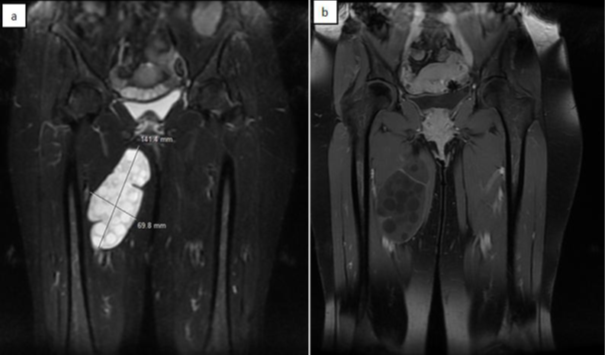

In our series, all the patients underwent an ultrasound of soft parts showing a HH stage III GHARBI classification in 87.5% of patients and stage I in a single patient. An MRI was performed in all our patients to determine the number, size, topography, and relationships with the vasculoneural pedicles (Figure 6). Abdominal ultrasound and chest X-rays Returning with no particularity in all patients. In our series, all patients underwent surgical resection without breaking the shell, except in a single patient where the cyst was ruptured. Two patients required a supplement by medical treatment, the first operated for recurrence and the second after rupture of the cyst. The macroscopic appearance of hydatidosis is often typical at the opening of the operative specimen showing numerous vesicles and false membranes, which confirms the histological study. The average follow-up in our series is 27.5 months with a minimum of 12 months and a maximum of 5 years. All our patients had simple postoperative follow-up and they did not present any significant complications, and didn’t present a recurrence so far.

Figure 6 Hydatid cyst in T1 hypointense and T2 hyperintense.